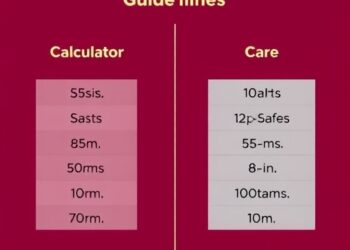

Early-Onset Sepsis: Calculator vs. Guidelines vs. Care

In a groundbreaking new study poised to reshape neonatal care practices, researchers have undertaken a meticulous comparison between established methods...